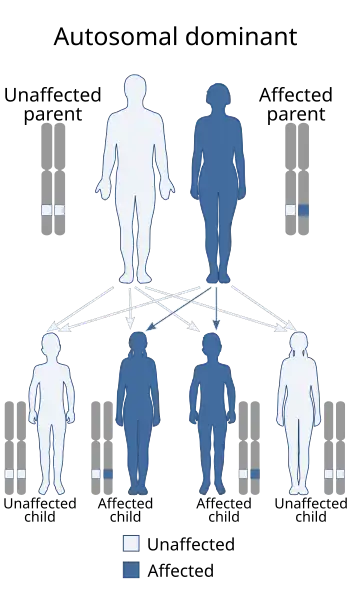

| Sotos syndrome is an autosomal dominant inherited condition | |

About 95 percent of Sotos syndrome cases occur by spontaneous mutation. Most of these cases result from new mutations involving the NSD1 gene. A few families have been described with more than one affected family member. These inherited cases enabled researchers to determine that Sotos syndrome has an autosomal dominant pattern of inheritance.